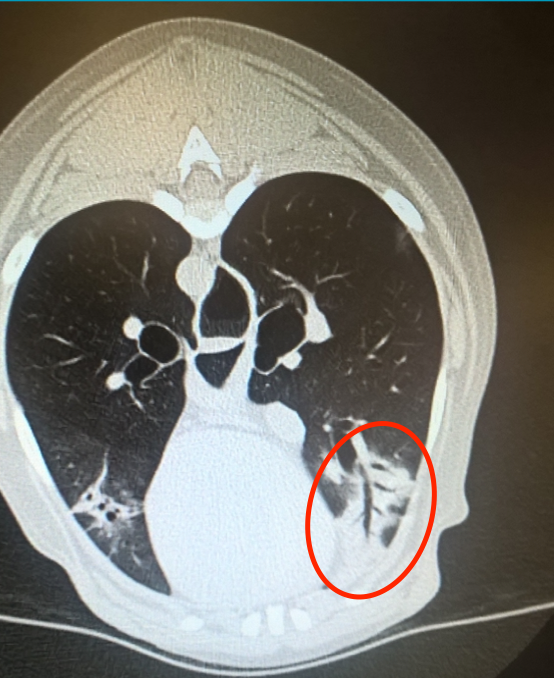

What finding is circled here?

Air bronchogram

What is an air bronchogram and when would you see it?

Air bronchogram: the phenomenon of air-filled bronchi (dark) being made visible by the opacification of surrounding alveoli.

Air bronchograms classically appear with alveolar disease (i.e. alveoli get filled with something).

However, we can also see them in interstitial disease, e.g. where there has been compressive atelectasis and crowding of tissue around open airways.